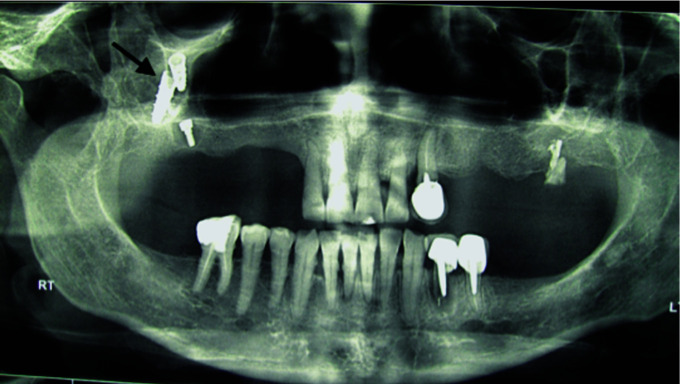

The use of dental implants to restore edentulous jaws has become commonplace. Usually, in the maxilla, following a tooth extraction, the height of alveolar bone decreases. This alteration in bone increases the risk of implants migrating into the sinus. In general, Caldwell-Luc and endoscopic surgery are performed to retrieve dental implants. In this case series, we collected data from 39 patients who had the complication of implant displacement within the maxillary sinus for 25 years. All the implants were removed using the Caldwell-Luc technique. Implant migration happened following functional loading, during the prosthetic procedure, due to lack of osseointegration in 3 patients, and during implant placement into the fresh socket in 3 patients. In the remaining cases, migration occurred preoperatively or postoperatively and prior to implant loading. Insufficient bone quantity is sometimes causing the implant to migrate to the maxillary sinus. In case of minimal bone height, a sinus lift before implant placement should be conducted. Retrieval of an implant pushed inside the maxillary antrum using the Caldwell Luc approach proved to be a reliable technique.